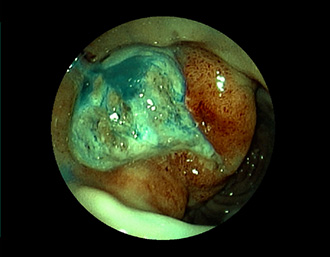

(インジゴカルミン散布画像)

(FICE+インジゴカルミン散布画像)